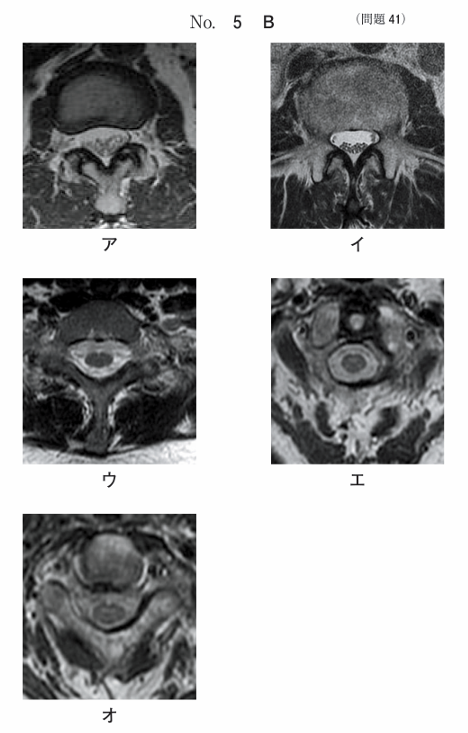

午前/問題41

脊椎のMR像別冊No. 5Aを別に示す。位置決め像の断面で得られる画像別冊No. 5Bはどれか。

1.ア

2.イ

3.ウ

4.エ

5.オ